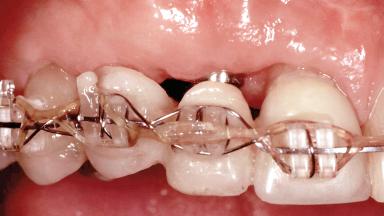

In 2001, a 48-year-old woman presented at a dental clinic with a failing fixed partial denture spanning from teeth 13 to 21. She was experiencing pain upon function, tenderness to palpation facial to tooth 13, and severe mobility of the prosthesis. Radiographic and clinical assessment revealed a subcrestal fracture of tooth 13, making its restoration unlikely. It was determined by the clinician that the tooth needed to be extracted prior to proceeding any further with dental care. After the extraction, the patient lost confidence in the progression of her treatment and sought consultation at the Center for Implant Dentistry. At her consultation visit in our clinic, an extra- and intraoral clinical examination revealed a medium lip line at full smile and an edentulous area spanning from 13 to 12 with both vertical and horizontal deficits in hard and soft tissue.

Type of Implants One-Piece|Reduced-Diameter

Bone Augmentation Horizontal|Staged|Vertical

Soft Tissue Grafting Staged